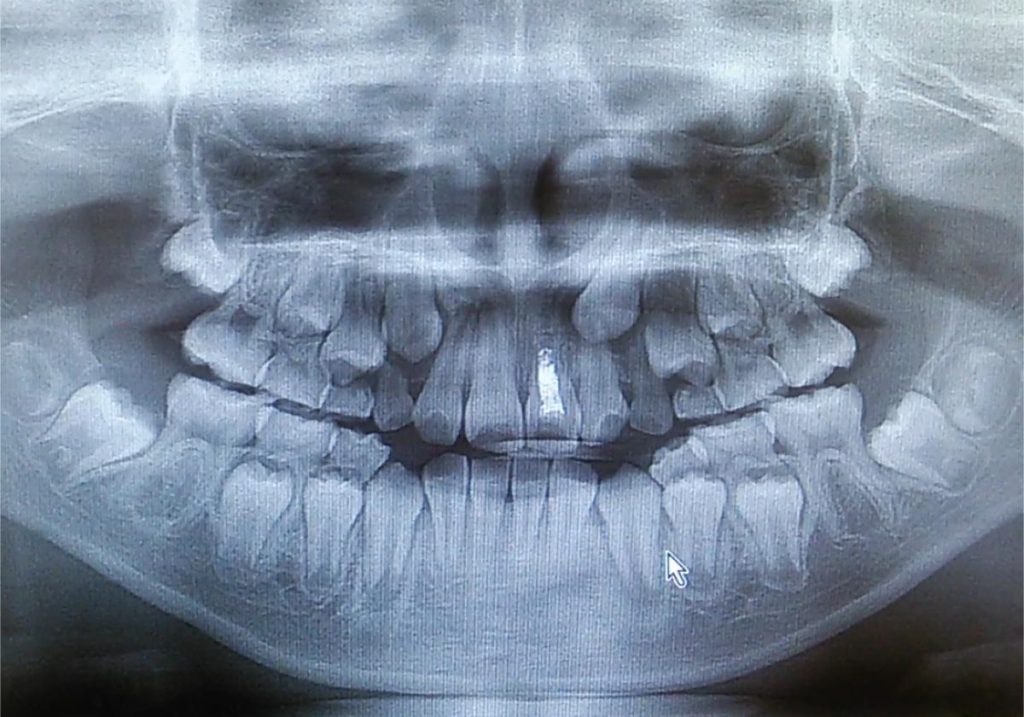

二期治療は、小児矯正において永久歯が生え揃う時期に実施される治療であり、子どもの成長に合わせた最終的な歯列調整を行います。ここでは、二期治療の役割について詳しく解説していきます。

二期治療の主な目的は、永久歯の並びを整え、噛み合わせを最適化することです。成長期の途中で行われる一期治療が顎の骨やスペースの確保を中心とした治療であるのに対し、二期治療では永久歯が適切な位置に生えるよう細かい調整を行います。この治療により、見た目の改善だけでなく、正しい噛み合わせが実現され、咀嚼や発音、さらには顔のバランスにおいても重要な効果をもたらします。

子どもの成長過程で発生する問題には、歯並びの乱れや噛み合わせのズレ、さらには顎の成長不足や過成長があります。これらの問題は、永久歯列が完成する段階で適切に対応する必要があります。例えば、放置された不正咬合は、将来的に顎関節症や歯の過剰な摩耗を引き起こす可能性があります。二期治療では、これらのリスクを未然に防ぎ、長期的な口腔の健康を守る役割を果たします。

二期治療では、固定式のブラケット装置や取り外し可能なマウスピース型装置が使用されます。これらの装置を用いることで、永久歯の細かな位置調整が可能となります。また、治療期間中は子どもの成長に合わせた定期的な調整を行うため、適切なタイミングで治療を進めることができます。この段階での治療の成否は、矯正の最終的な結果を大きく左右するため、治療計画の立案と実行が非常に重要です。

二期治療は、永久歯が生え揃ったタイミングで開始されます。この治療の主な目的は、永久歯の位置を細かく調整し、歯列全体を整えることです。一期治療で作られた顎のスペースを活かし、ブラケットやマウスピースなどを用いて歯の位置や噛み合わせを最終的に仕上げます。二期治療は、見た目の改善だけでなく、正しい噛み合わせを実現することで、咀嚼効率や発音、さらには顎関節への負担を軽減する役割も果たします。